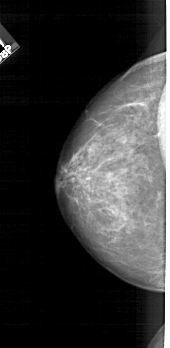

A_1715_1.RIGHT_MLO

RIGHT_MLO LINES 5491 PIXELS_PER_LINE 2386 BITS_PER_PIXEL 12 RESOLUTION 43.5 OVERLAY